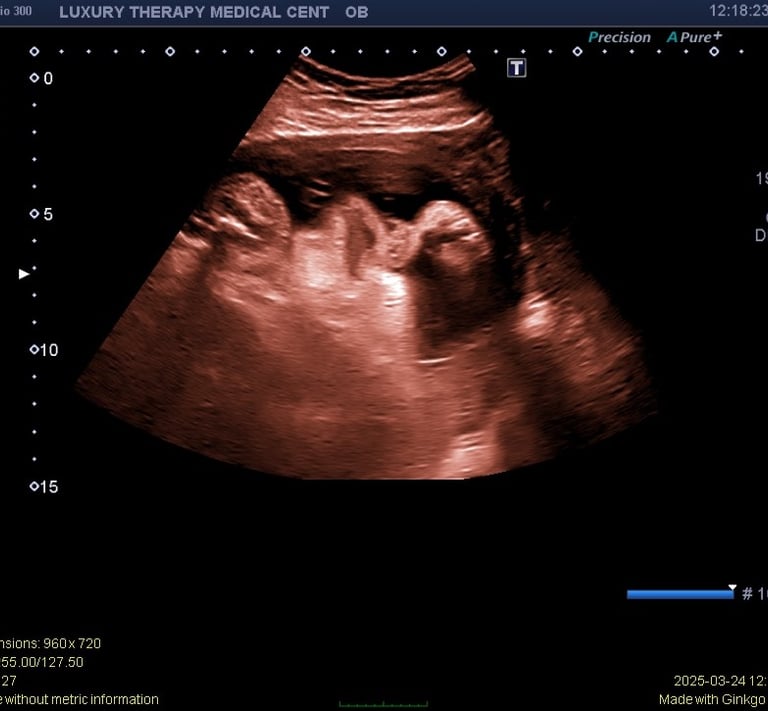

A complete obstetric ultrasound is a detailed imaging exam used to evaluate the baby and the uterus during pregnancy. This ultrasound helps healthcare providers assess fetal development and identify important pregnancy milestones.

A complete OB ultrasound may evaluate:

Fetal growth and development

Fetal heartbeat

Gestational age

Position of the baby

Placenta location

Amniotic fluid levels

This examination provides important information about the progress of the pregnancy.

Ultrasound images of the uterus and baby are obtained

Measurements of fetal growth may be taken

The baby’s position and development are evaluated